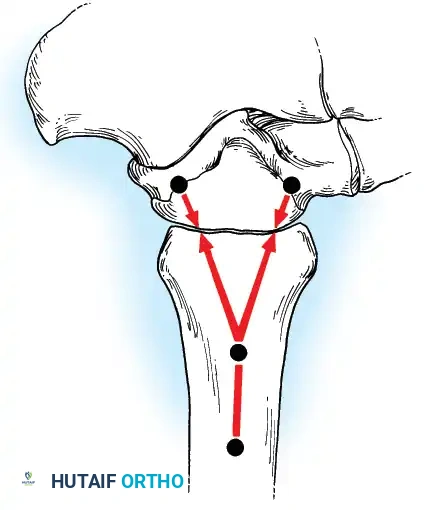

Internal fixation is currently the preferred method for uncomplicated ankle arthrodesis due to higher union rates, superior patient comfort, and the elimination of pin-tract infections. Biomechanical studies demonstrate that crossed, large-diameter (6.5 mm or 7.3 mm) cannulated cancellous screws provide exceptional resistance to shear and torsional forces.

A standard construct involves two or three screws:

1. A "home run" screw directed from the posterior malleolus into the anterior neck of the talus.

2. A screw from the medial malleolus into the lateral body of the talus.

3. A screw from the anterolateral tibia into the medial talar body.

In cases of severe osteopenia or when extending the fusion to the subtalar joint (Tibiotalocalcaneal Arthrodesis), retrograde intramedullary nailing provides a load-sharing construct with superior bending stiffness.

The optimal position for knee arthrodesis is 10 to 15 degrees of flexion and 5 to 7 degrees of valgus. This slight flexion assists in foot clearance during the swing phase of gait and makes sitting in confined spaces more manageable. A perfectly straight (0 degrees) knee is cosmetically awkward and functionally detrimental, causing a vaulting gait pattern.